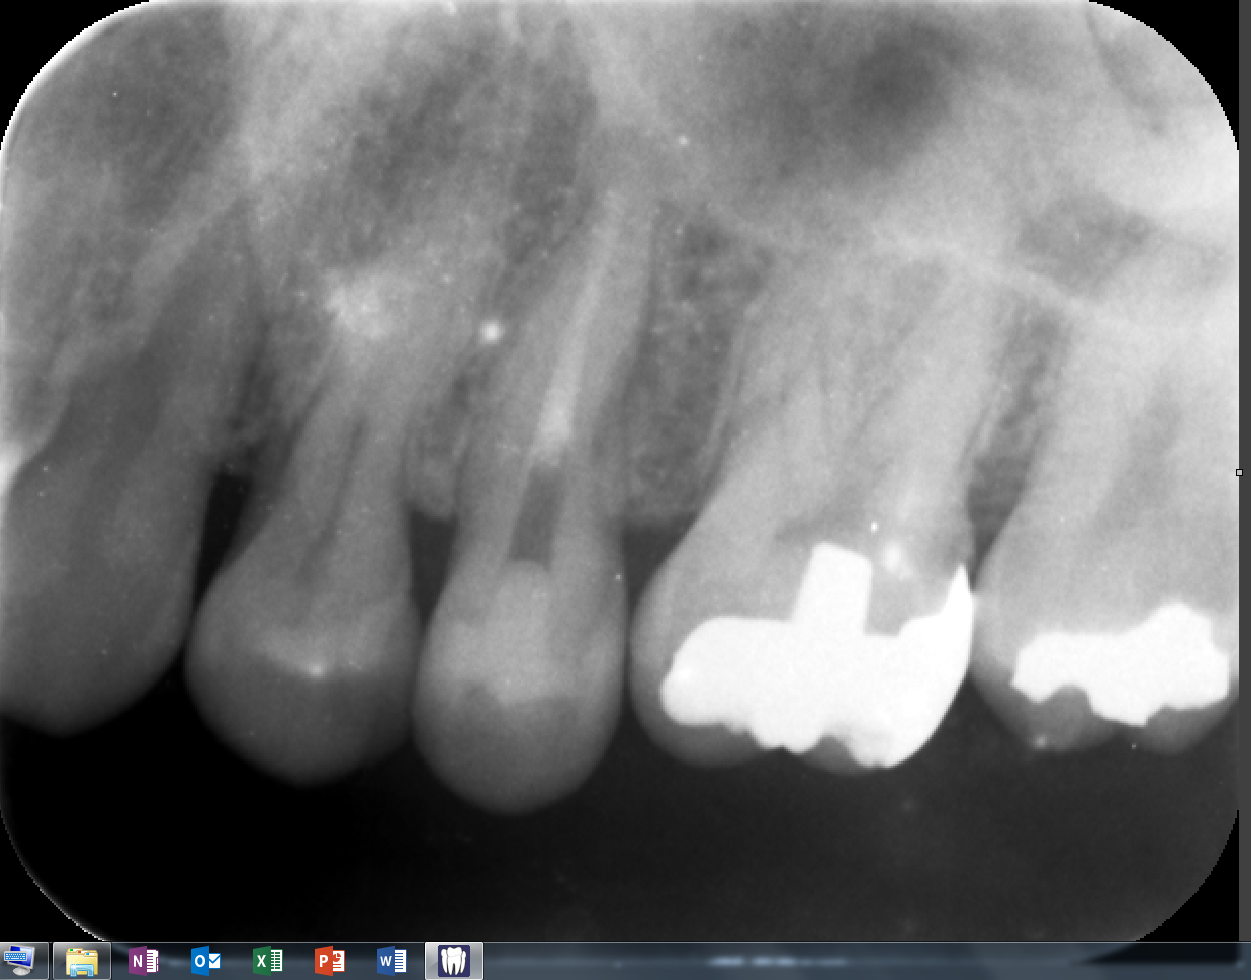

2ケース目このケースも

ストレートラインアクセス。

根管形成終了

MTAで根管充填